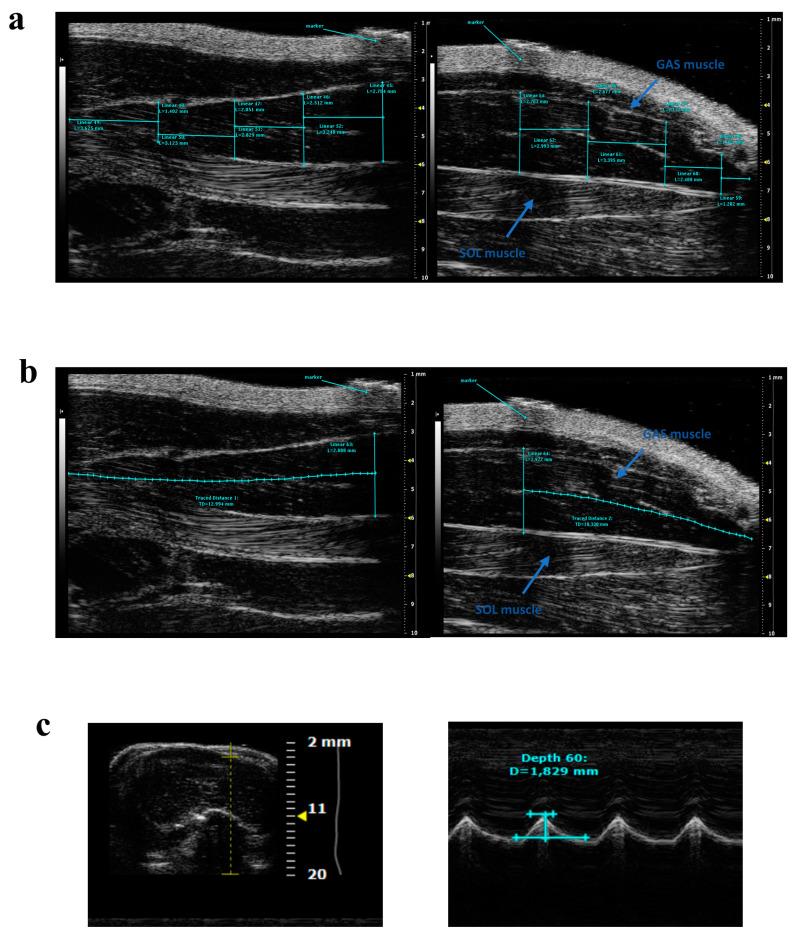

Ultrasonography is a safe, non-invasive imaging technique used in several fields of medicine, offering the possibility to longitudinally monitor disease progression and treatment efficacy over time. This is particularly useful when a close follow-up is required, or in patients with pacemakers (not suitable for magnetic resonance imaging). By virtue of these advantages, ultrasonography is commonly used to detect multiple skeletal muscle structural and functional parameters in sports medicine, as well as in neuromuscular disorders, e.g., myotonic dystrophy and Duchenne muscular dystrophy (DMD). The recent development of high-resolution ultrasound devices allowed the use of this technique in preclinical settings, particularly for echocardiographic assessments that make use of specific guidelines, currently lacking for skeletal muscle measurements. In this review, we describe the state of the art for ultrasound skeletal muscle applications in preclinical studies conducted in small rodents, aiming to provide the scientific community with necessary information to support an independent validation of these procedures for the achievement of standard protocols and reference values useful in translational research on neuromuscular disorders.

超声成像是一种安全、非侵入性的医学成像技术,可用于多个医学领域,能够随时间纵向监测疾病的进展和治疗效果。当需要密切随访或在装有起搏器的患者(不适合磁共振成像)中时,这尤其有用。由于这些优势,超声检查常用于运动医学中检测多种骨骼肌结构和功能参数,以及神经肌肉疾病,例如肌强直性营养不良和杜氏肌营养不良症(DMD)。高分辨率超声设备的最新发展使得该技术可用于临床前研究,特别是用于超声心动图评估,目前尚缺乏针对骨骼肌测量的具体指南。在这篇综述中,我们描述了在小型啮齿动物中进行的临床前研究中超声骨骼肌应用的最新技术,旨在为科学界提供必要的信息,以支持对这些程序进行独立验证,从而制定用于神经肌肉疾病转化研究的标准方案和参考值。